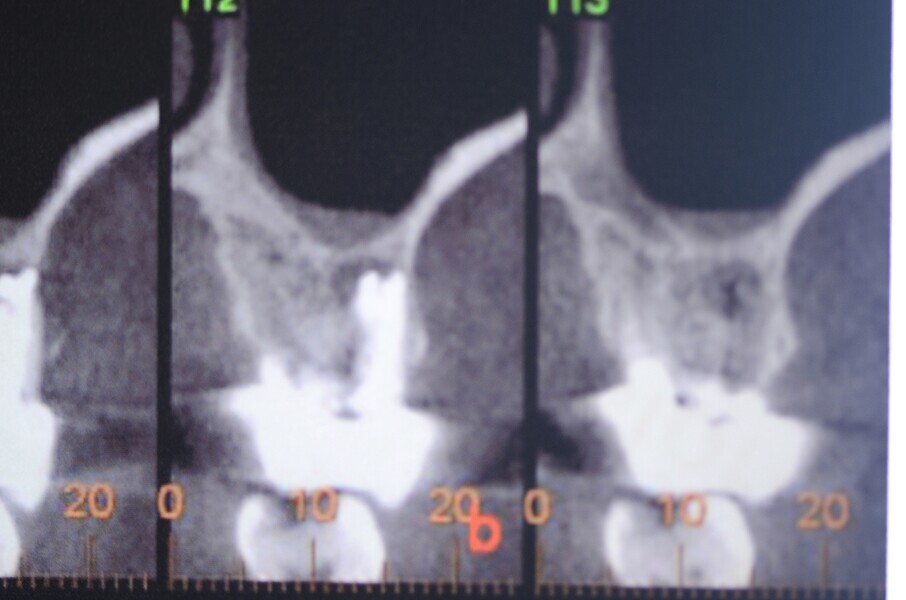

Fig. 35 : Région molaire édentée avant l’implantation.

Fig. 36 : Région molaire édentée avant l’implantation.

Fig. 44 : Radiographie de contrôle et excellente intégration de l’implant en céramique dans l’environnement parodontal.

Fig. 45 : Radiographie de contrôle et excellente intégration de l’implant en céramique dans l’environnement parodontal.

Un patient présentant un défaut infraosseux s’est présenté au cabinet dentaire avec le souhait explicite d’un traitement par un implant en zircone, pour remplacer l’une de ses molaires. Un implant deux pièces en zircone a donc été posé et le défaut infra-osseux a été traité dans le même temps, au moyen d’une allogreffe osseuse et du dérivé de matrice amélaire Emdogain (Straumann). La mise en charge n’a pas été réalisée à ce stade (Figs. 35–45).